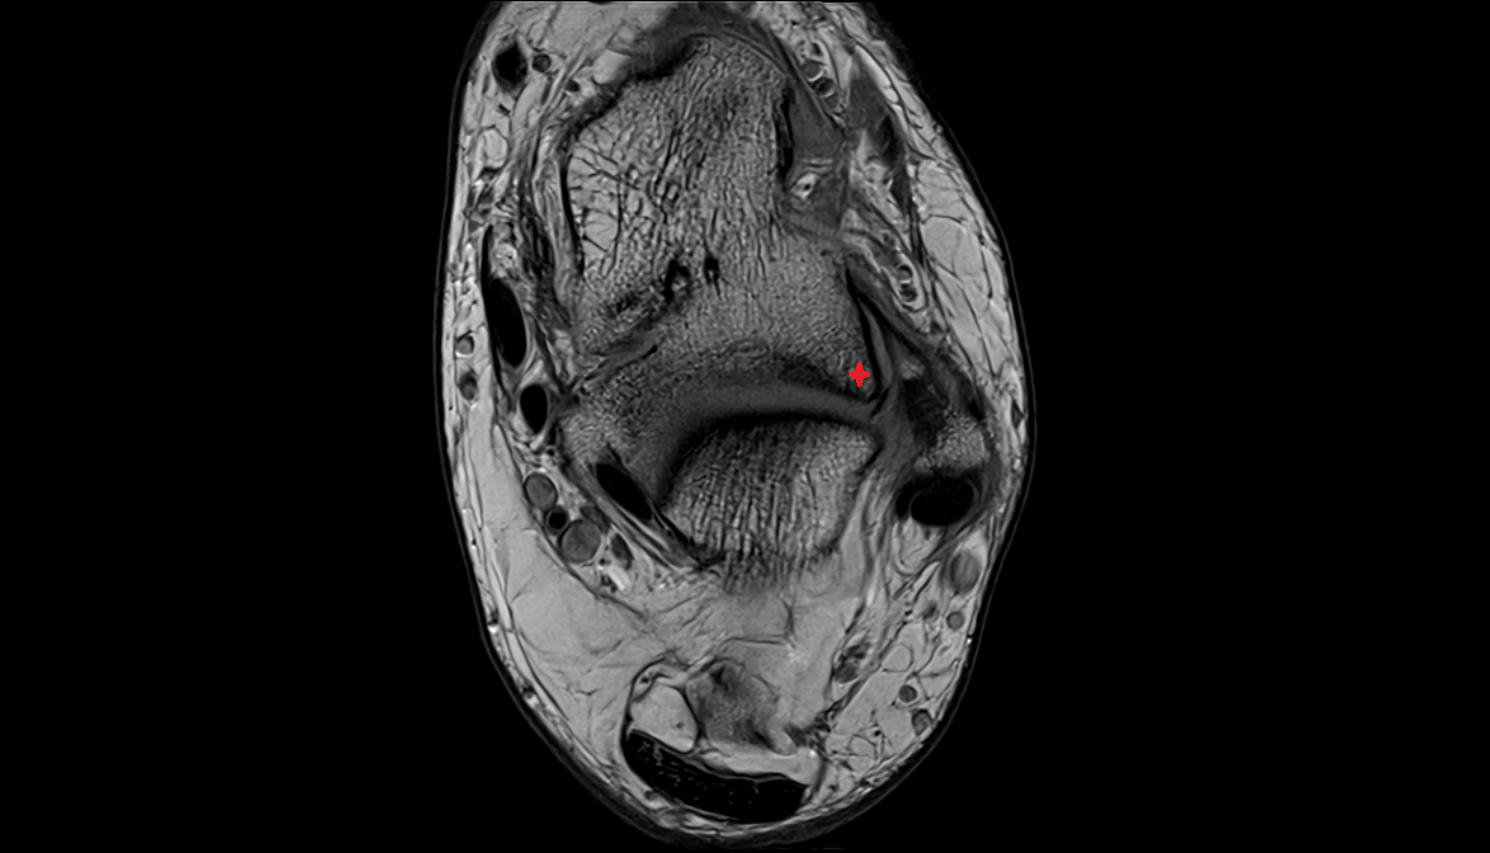

- Medial meniscus

- Lateral meniscus

- Anterior horn of medial meniscus

- Posterior horn of medial meniscus

- Body of medial meniscus

- Anterior root of medial meniscus

- Posterior root of medial meniscus

- Anterior horn of lateral meniscus

- Posterior horn of lateral meniscus

- Body of lateral meniscus

- Anterior root of lateral meniscus

- Posterior root of lateral meniscus

- Knee Joint